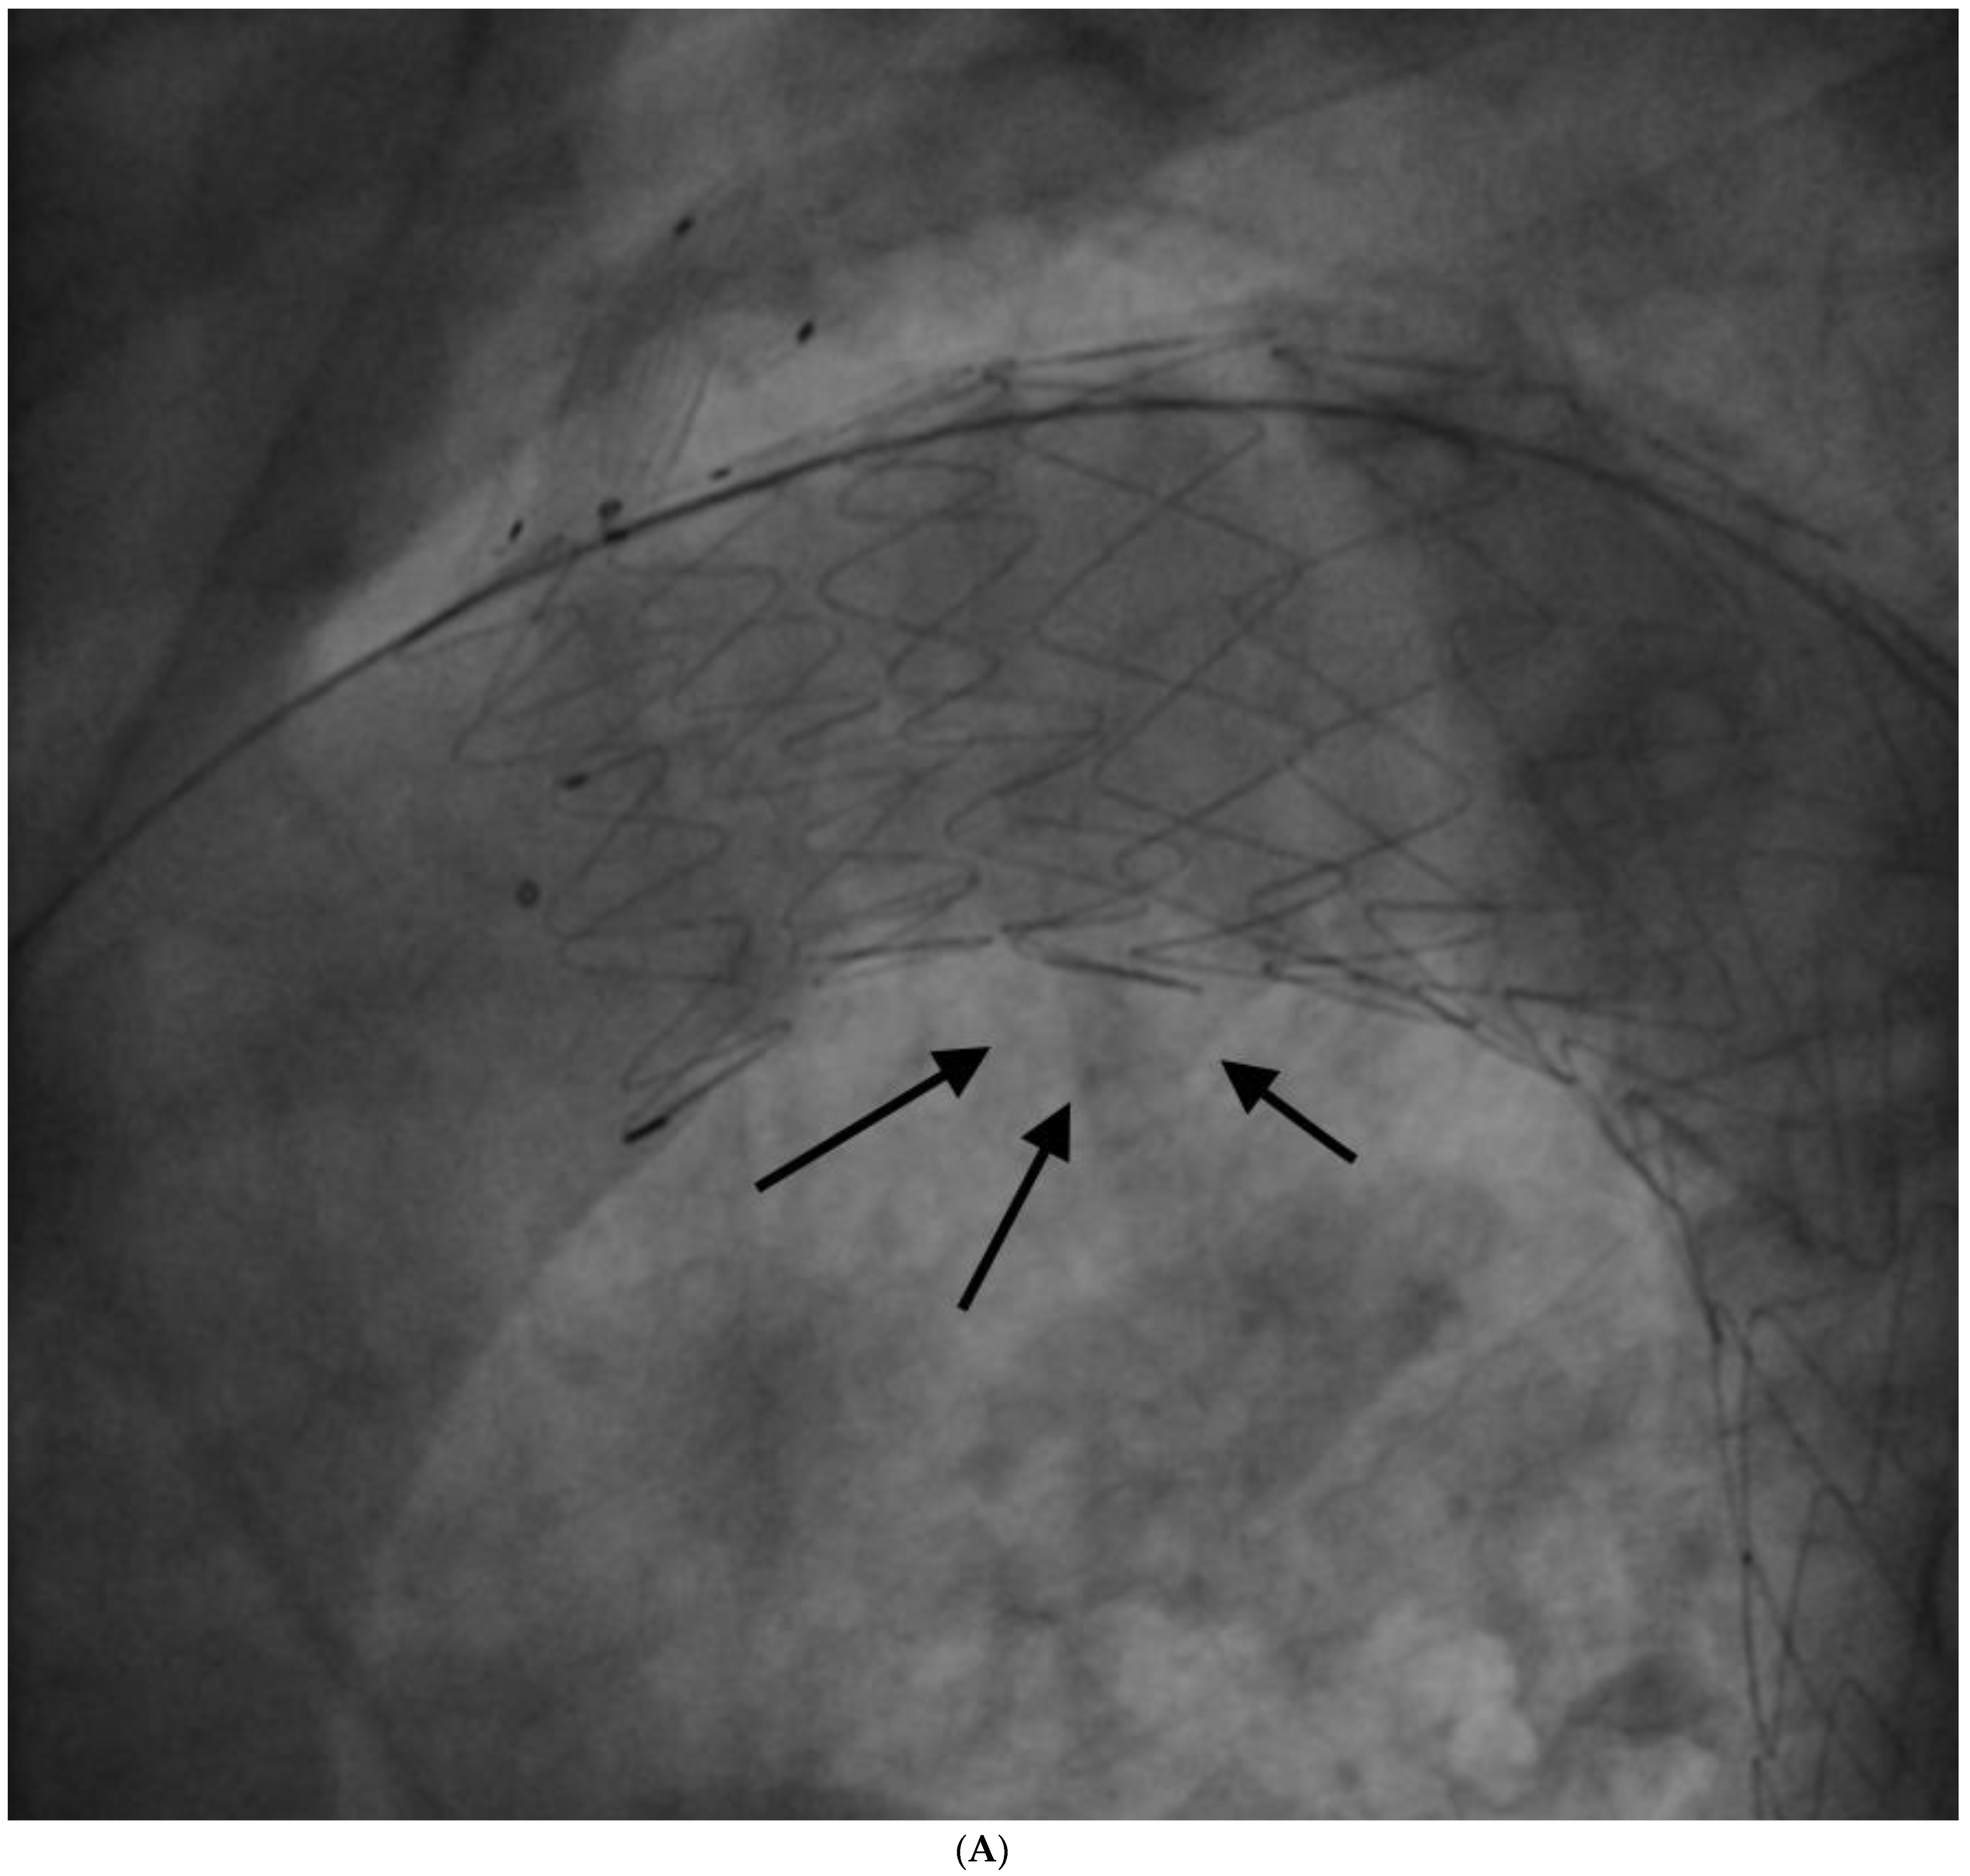

The procedure was performed in deep sedation. A 6 F pigtail was advanced through a right radial arterial access into the ascending aorta for aortic angiographies; then a 10 F right femoral arterial access was obtained with the pre-implantation of two percutaneous closure systems, and subsequently. upgraded to 18 F. Afterwards, an 8 F left brachial arterial access was obtained; a guidewire was advanced through the brachial access into the femoral access, forming a brachial–femoral loop; a dedicated catheter was advanced on the guidewire; then, an extra stiff guidewire (0.035″) was advanced through femoral access to ascending aorta, and the branch guidewire was positioned in the catheter introduced from the brachial access. A Castor 38 mm × 32 mm × 200 mm stent graft with a 12 mm × 25 mm branch for LSA was positioned and released at PAU level. The final angiography showed the exclusion of PAU, but also a small type 1 endoleak (Figure 5A) treated successfully with some balloon dilatations in the proximal graft lumen (Reliant Balloon, Figure 5B,C). This finding is likely due to graft malapposition caused by an enlarged ascending aorta and aortic arch. There were no complications during the procedure. The patient was discharged with anti-hypertensive treatment (candesartan 16 mg, hydrochlorothiazide 12.5 mg, amlodipine 5 mg), aspirin, plus clopidogrel (for 3 months, followed by low-dose aspirin only).

Figure 5. (A)—Type I endoleak observed after graft deployment; black arrows show endoleak. (B)—Balloon inflation for type I endoleak treatment. (C)—Final result after balloon inflation; no endoleak is observed.